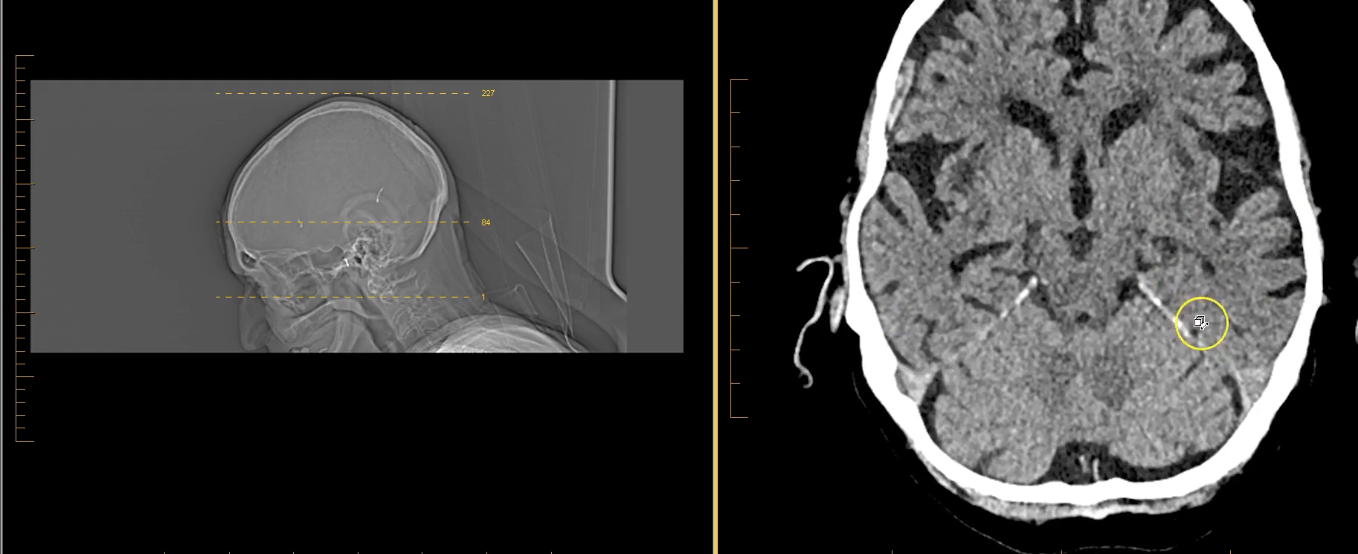

term image

calcified choroid plxus in lateral ventricles